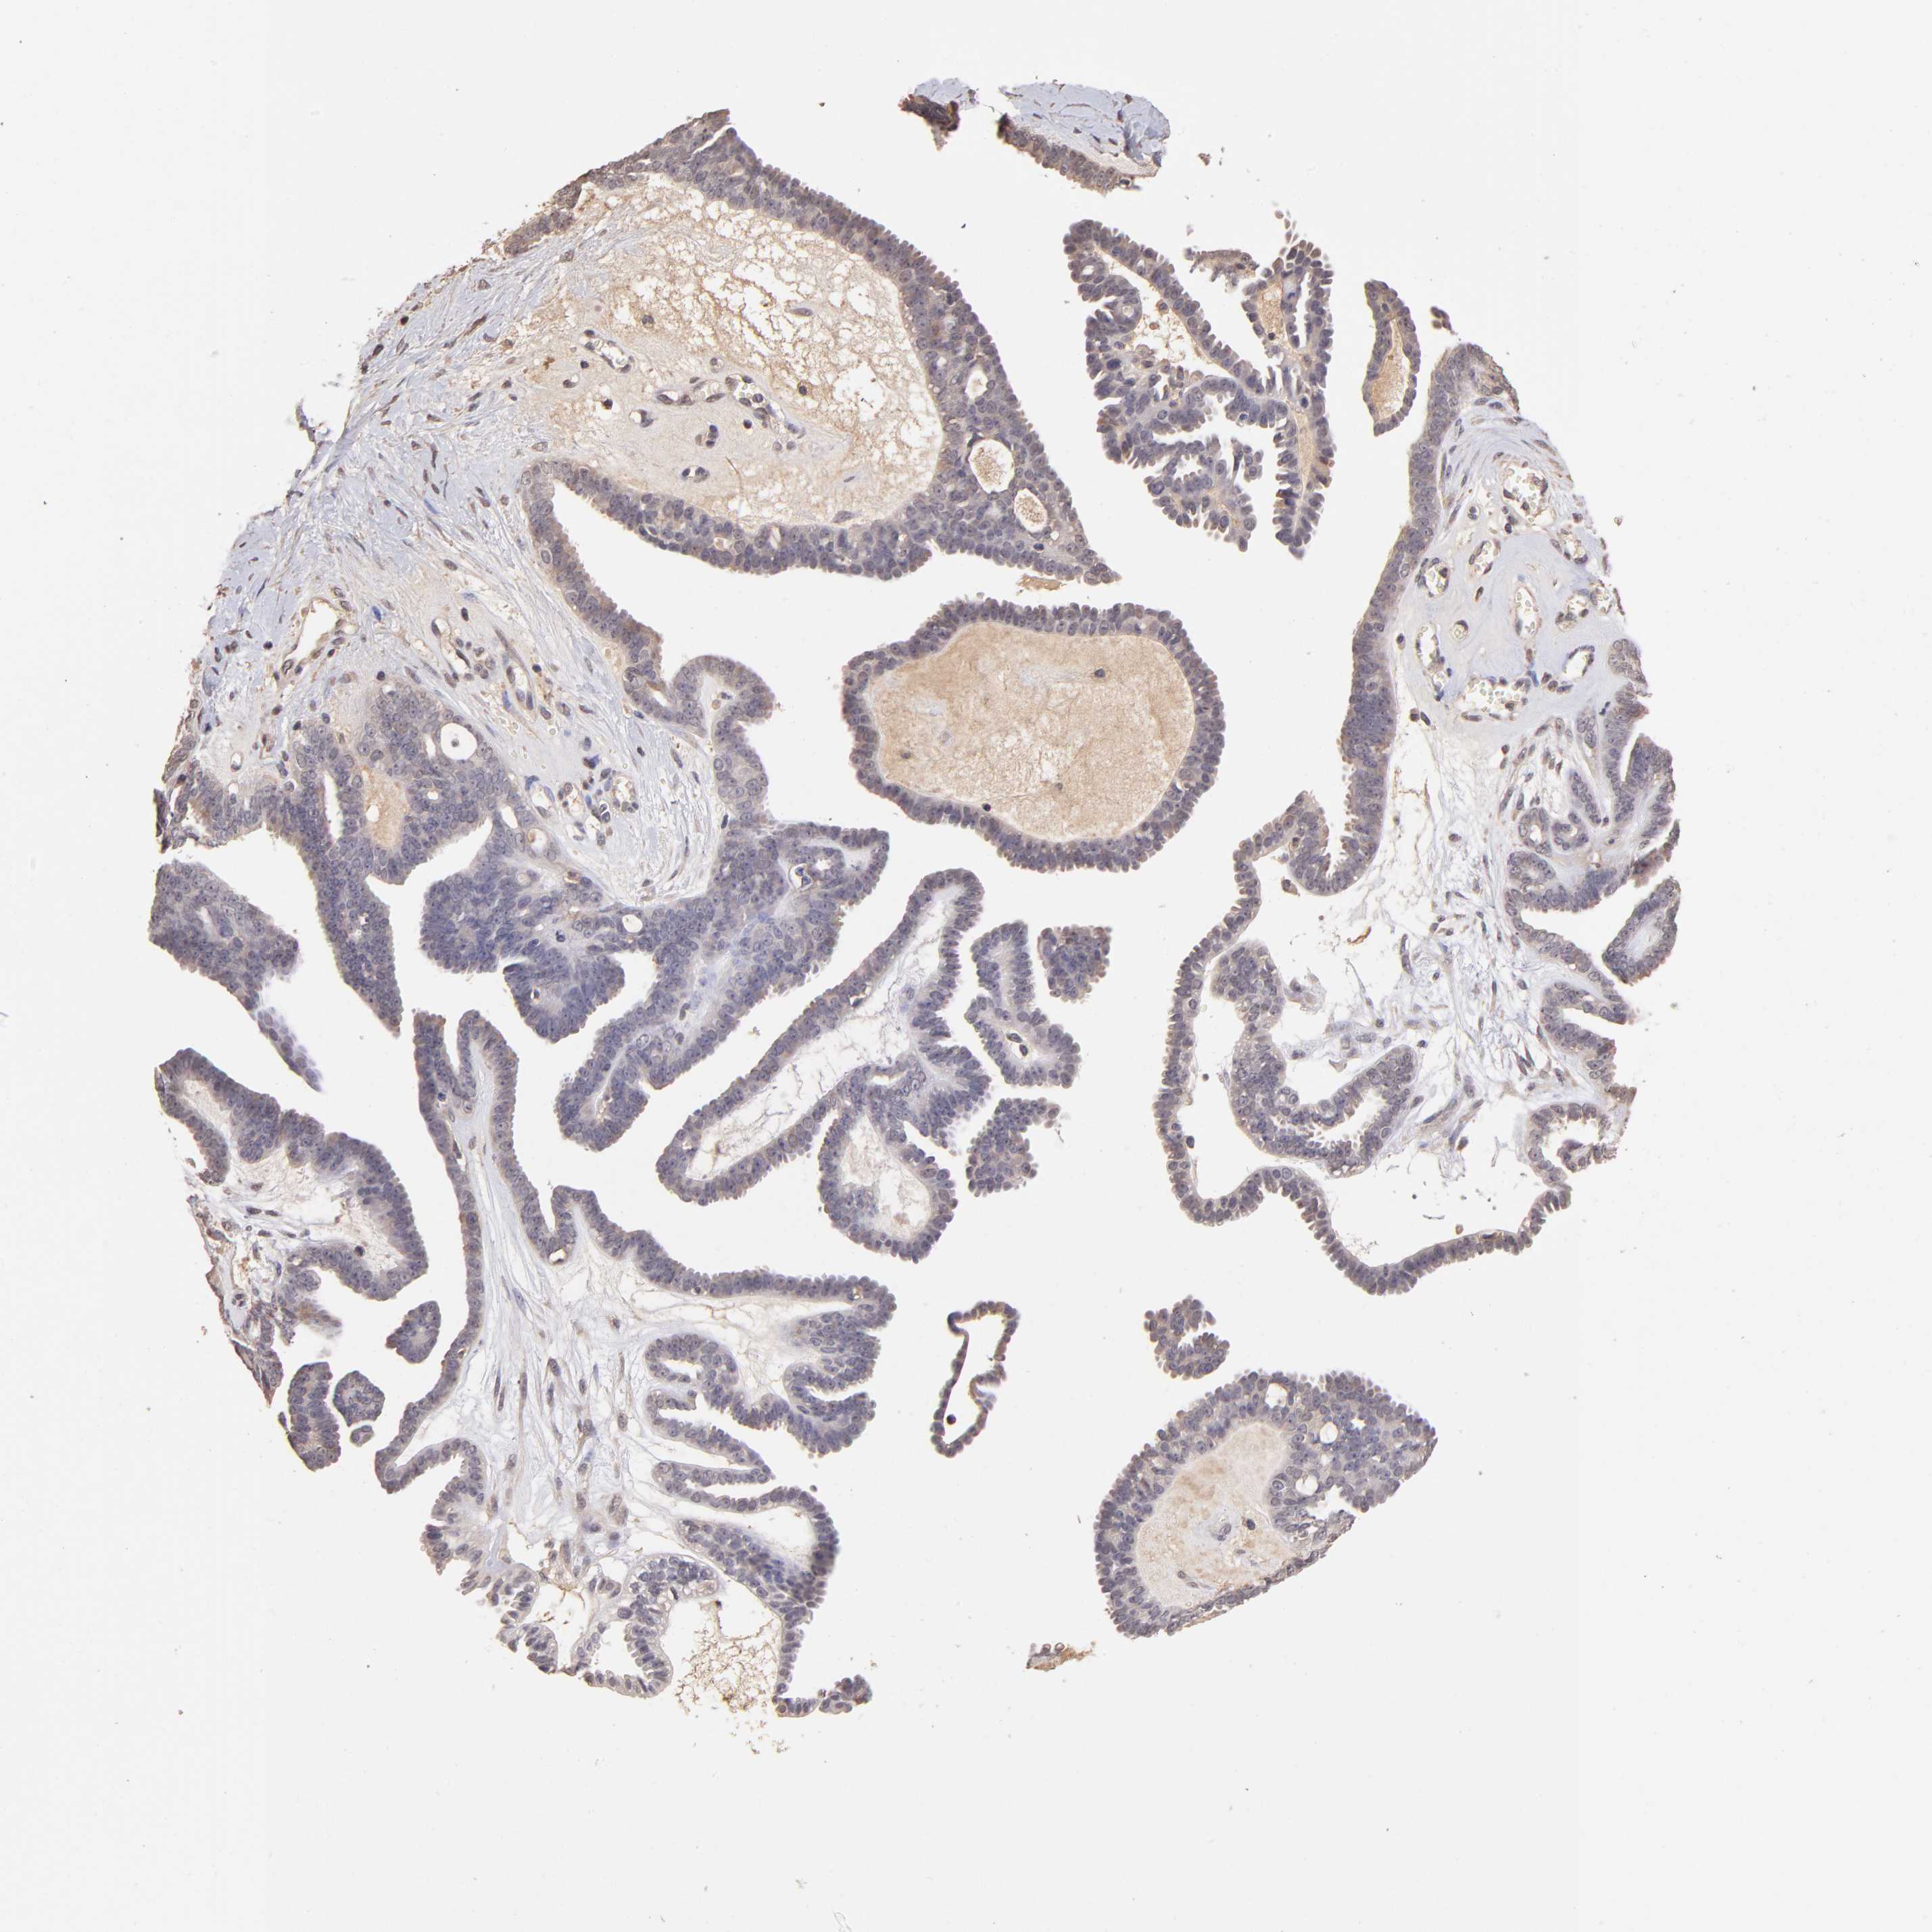

OVARIAN CANCER - Protein expressioni

A mouse-over function shows sample information and annotation data. Click on an image to view it in a full screen mode. Samples can be filtered based on level of antibody staining by selecting one or several of the following categories: high, medium, low and not detected. The assay and annotation is described here.

Note that samples used for immunohistochemistry by the Human Protein Atlas do not correspond to samples in the TCGA dataset.

Antibody stainingi

Antibody staining in the annotated cell types in the current human tissue is reported as not detected, low, medium, or high, based on conventional immunohistochemistry profiling in selected tissues. This score is based on the combination of the staining intensity and fraction of stained cells.

Each image is clickable and will lead to virtual microscopy that enables deeper exploration of all samples and also displays staining intensity scores, fraction scores and subcellular localization as well as patient and tissue information for each sample.

Antibody HPA002633

Antibody HPA046758

Antibody CAB010906

Carcinoma, endometroid

Cystadenocarcinoma, serous, NOS

Cystadenocarcinoma, mucinous, NOS

Carcinoma, NOS